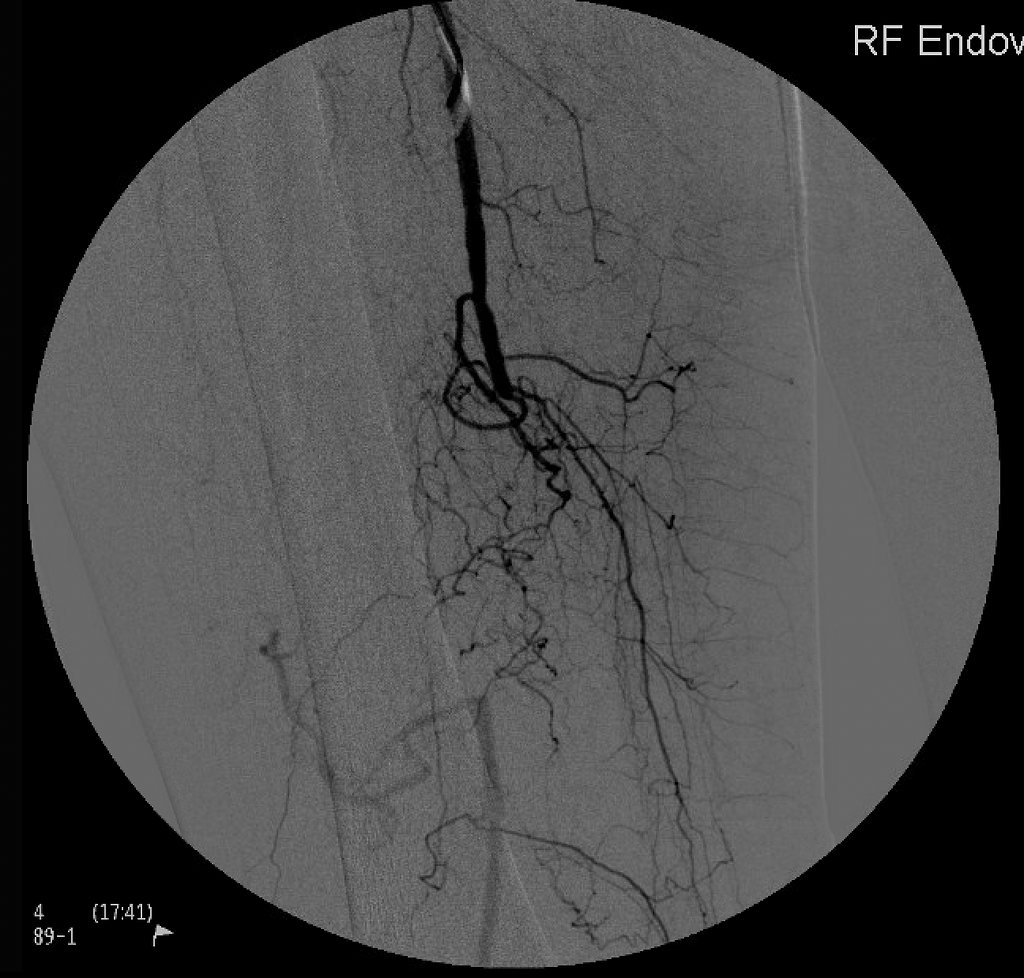

Endovascular treatment for arterial disease utilizes minimally invasive procedures, like angioplasty and stent placement, to restore and support blood flow, providing effective and targeted interventions for improved vascular health.